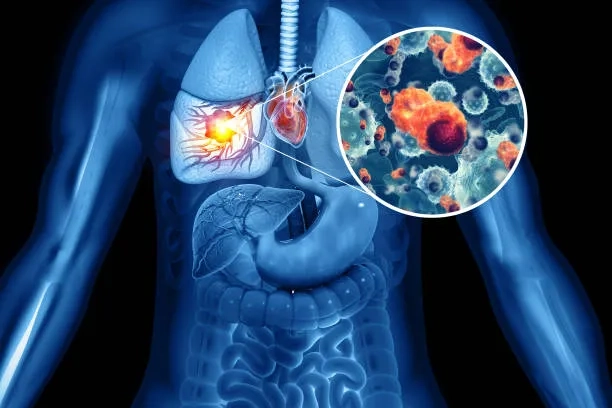

Image of the disease Lung Cancer - and other variables

Diagram explaining what is lung cancer